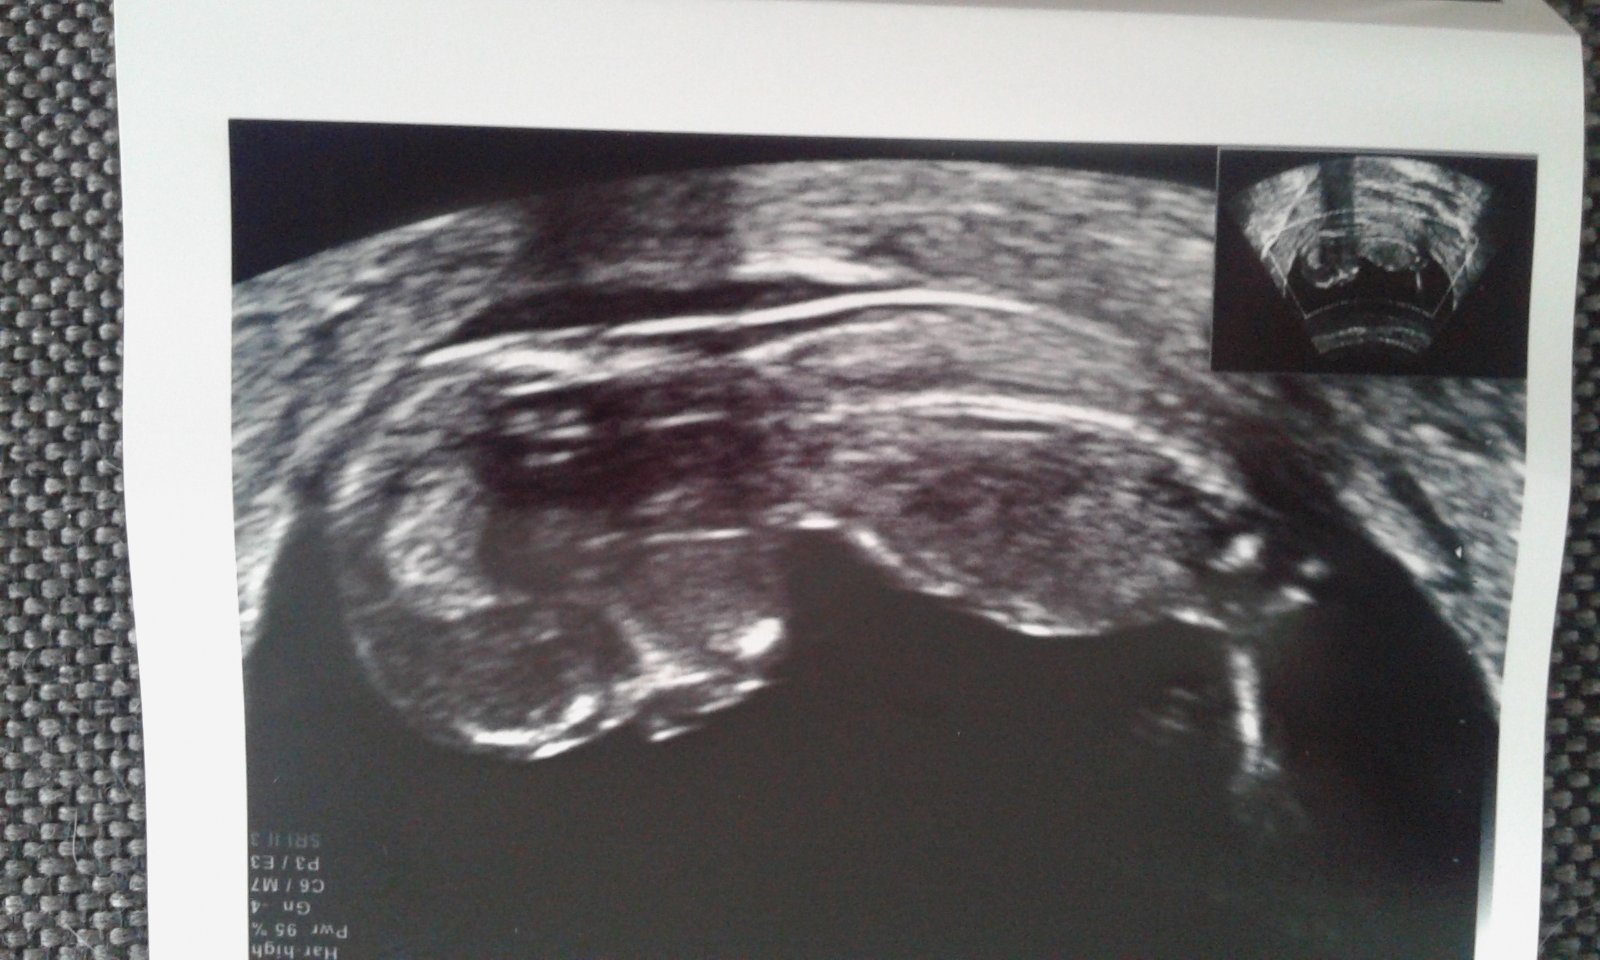

@leymea Jojo, diky moc 🙂 Je tam, kde ma byt. Kdyz se zobrazil nalez z vaginalni sondy na monitoru, byly videt dve dutinky. Tak ve me hrklo 🙂 Ale dr. rikal, ze to druhe je spise ten hematom. Zitra jdu jeste ke sve gynekolozce, ted jsem byla v CAR, kam jsem chodila, abych zjistila pricinu sveho rozhazeneho cyklu po porodu (tu historii urcite znas). Jinak cyklus se uz hodil do klidu, tohle tehotenstvi je uz z me fyziologicke delky 🙂 No, tak uvidim jeste zitra, co mi rekne druha lekarka, treba bude mit na hematom jiny nazor 😃

Hoja, tak dnesni kontrola byla ok. Hematom nikde 🙂 Dr. rikala, ze to mohl byt sliznicni hlen ci zvetsena cevka, nebo se pry vstrebal. Takze jsem bez hematomu s jednim GV o velikosti 8 mm. Ted mi volal ten prvni lekar, vcerejsi hCG 2510 mlU/mL. Jsem dnes 21 DPO, presne 3 tydny od poceti a celkem 44 DC. Odpovida to?

@sudylichozrout tak to jsou dobre zpravy 🙂 jeste posilam jednu fotku, ta prvni je vzhuru nohama, pritom ji mam v mobilu normalne 😀